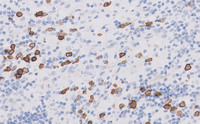

Figure 4-S100

The Rosai-Dorfman histiocytes are strongly positive for S100 with nuclear and cytoplasmic staining.  On higher power, emperipolesis with lymphocytes present in the cytoplasm of these histiocytes is apparent.  Emperipolesis is characteristic features in this disease.